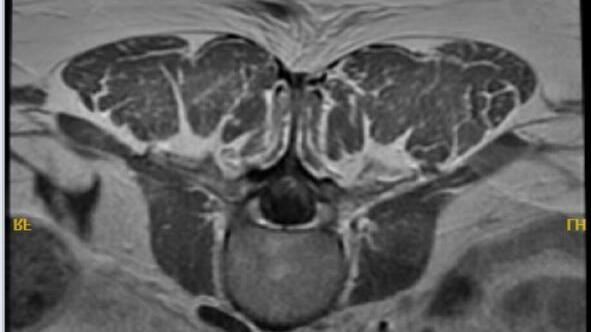

A RARE CASE OF ACUTE INFLAMMATORY DEMYELINATING POLYRADICULOPATHY FOLLOWING PFIZER COVID-19 VACCINE

Vincent Courant1 , Murilo Silva1, Satwant Grewal1, Margrit Wiesendanger2

1Mount Sinai Morningside-West Hospitals, Icahn School of Medicine at Mount Sinai, New York, NY, United States;

2Mount Sinai Hospital, Icahn School of Medicine at Mount Sinai, New York, NY, United States